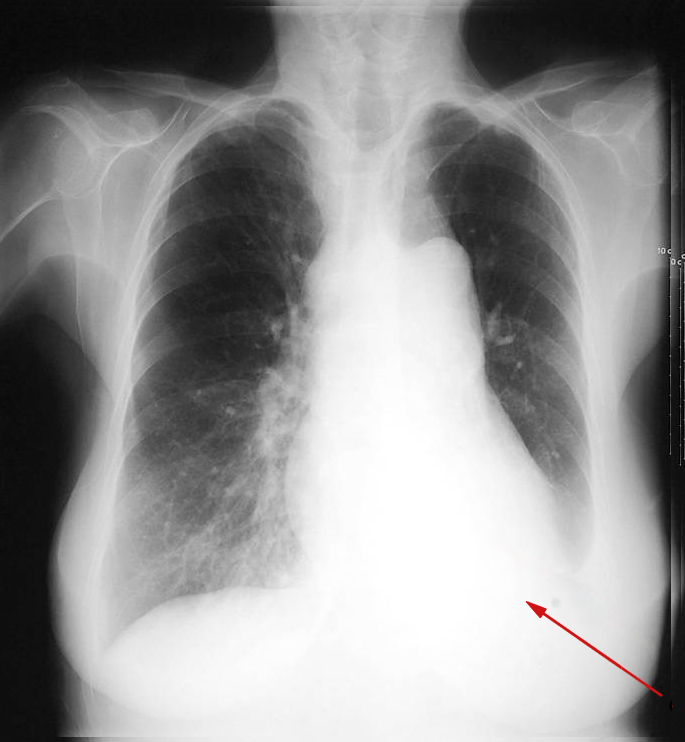

Røntgenundersøgelse af thorax kort tid efter en operation. Man kan ikke se den venstre diafragmakuppel (pilen peger på den manglende diafragmaskygge). Det skyldes en atelektase af den venstre underlap, som ikke længere ventileres. Venstre lunge er volumenformindsket, underlappen ses hvid på billedet (der er ikke luft i den aktuelt).